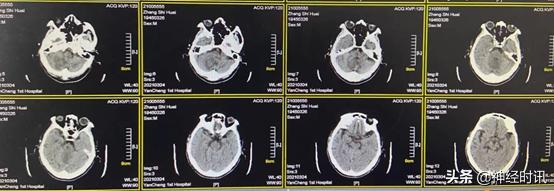

入院3 d后(1月21日),急诊头颅CT提示小脑内仍有大量血肿存在

1月26日(脑血疏用药5 d后)复查CT,患者小脑血肿开始逐渐淡化,血肿量明显减少,约20 ml,周围水肿并不明显,且环池变得清楚,继续服用脑血疏口服液

2月1日(脑血疏用药10 d后)复查CT,显示患者小脑血肿进一步淡化吸收,血肿量约15 ml,脑干及环池显示完全,效果明显,继续服用脑血疏口服液